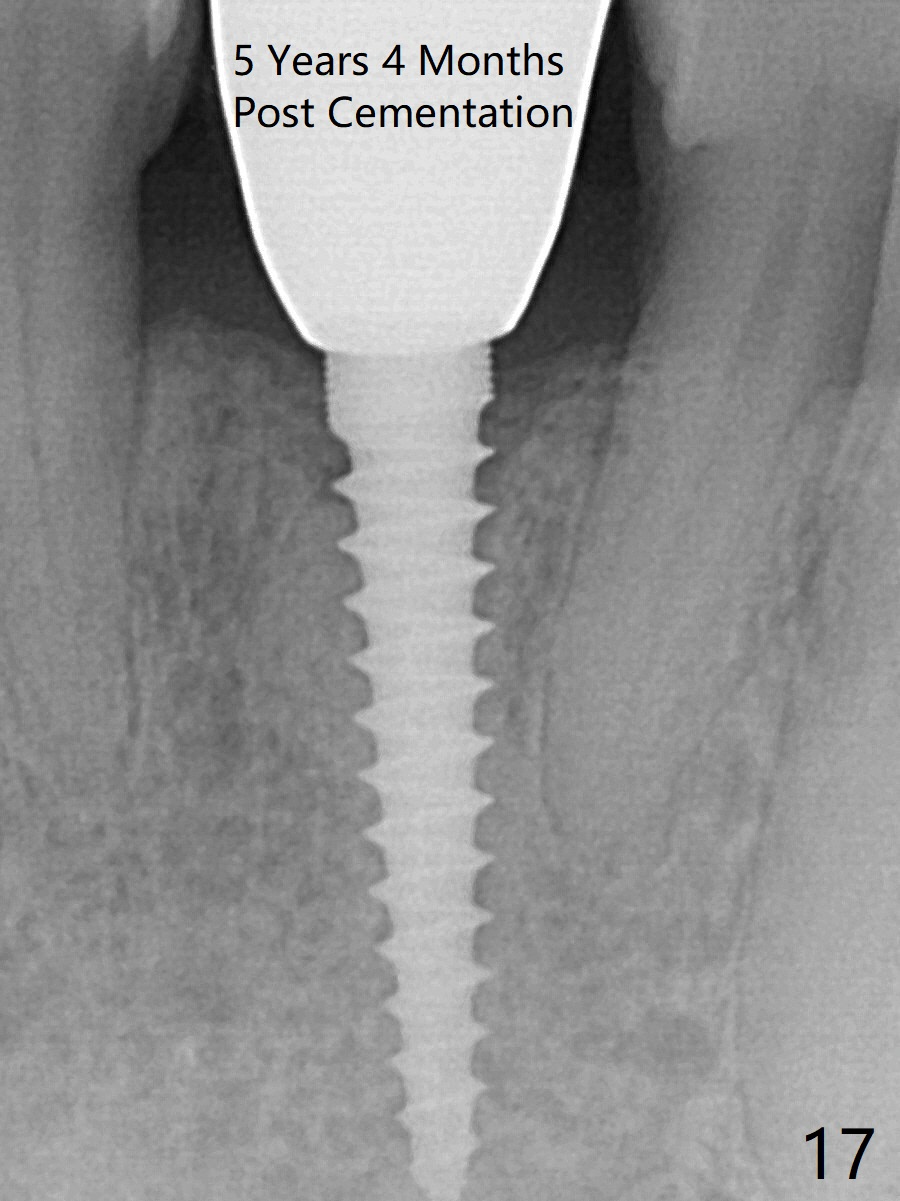

Fig.10,11 show 7 day follow up.  The permanent crown is seated 4.5 months postop (Fig.12).  Minimal bone resorption occurs at the crest 4 months postop (Fig.13), which is most likely associated with conservative approach (flapless).  The patient returns for follow up 2.5 months post cementation (Fig.14,15).  The implant remains in the bone 4 years post cementation (Fig.16 CT coronal section; lingual thread exposure, corresponding to preop defect in Fig.1).   There is mild coronal bone resorption 5 years 4 months post cementation (Fig.17).